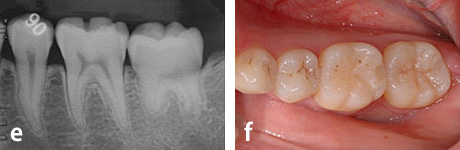

第二大臼歯部への親知らずの移植

a、b: 治療前。16歳、少女。

第二大臼歯が吸収を受けており保存が不可能でした。そこで、隣接する親知らずを同部へ移植することにしました。

c : 移植直後

d : 移植後3ヶ月

e、f : 移植後6ヶ月

g、h : 移植後3年